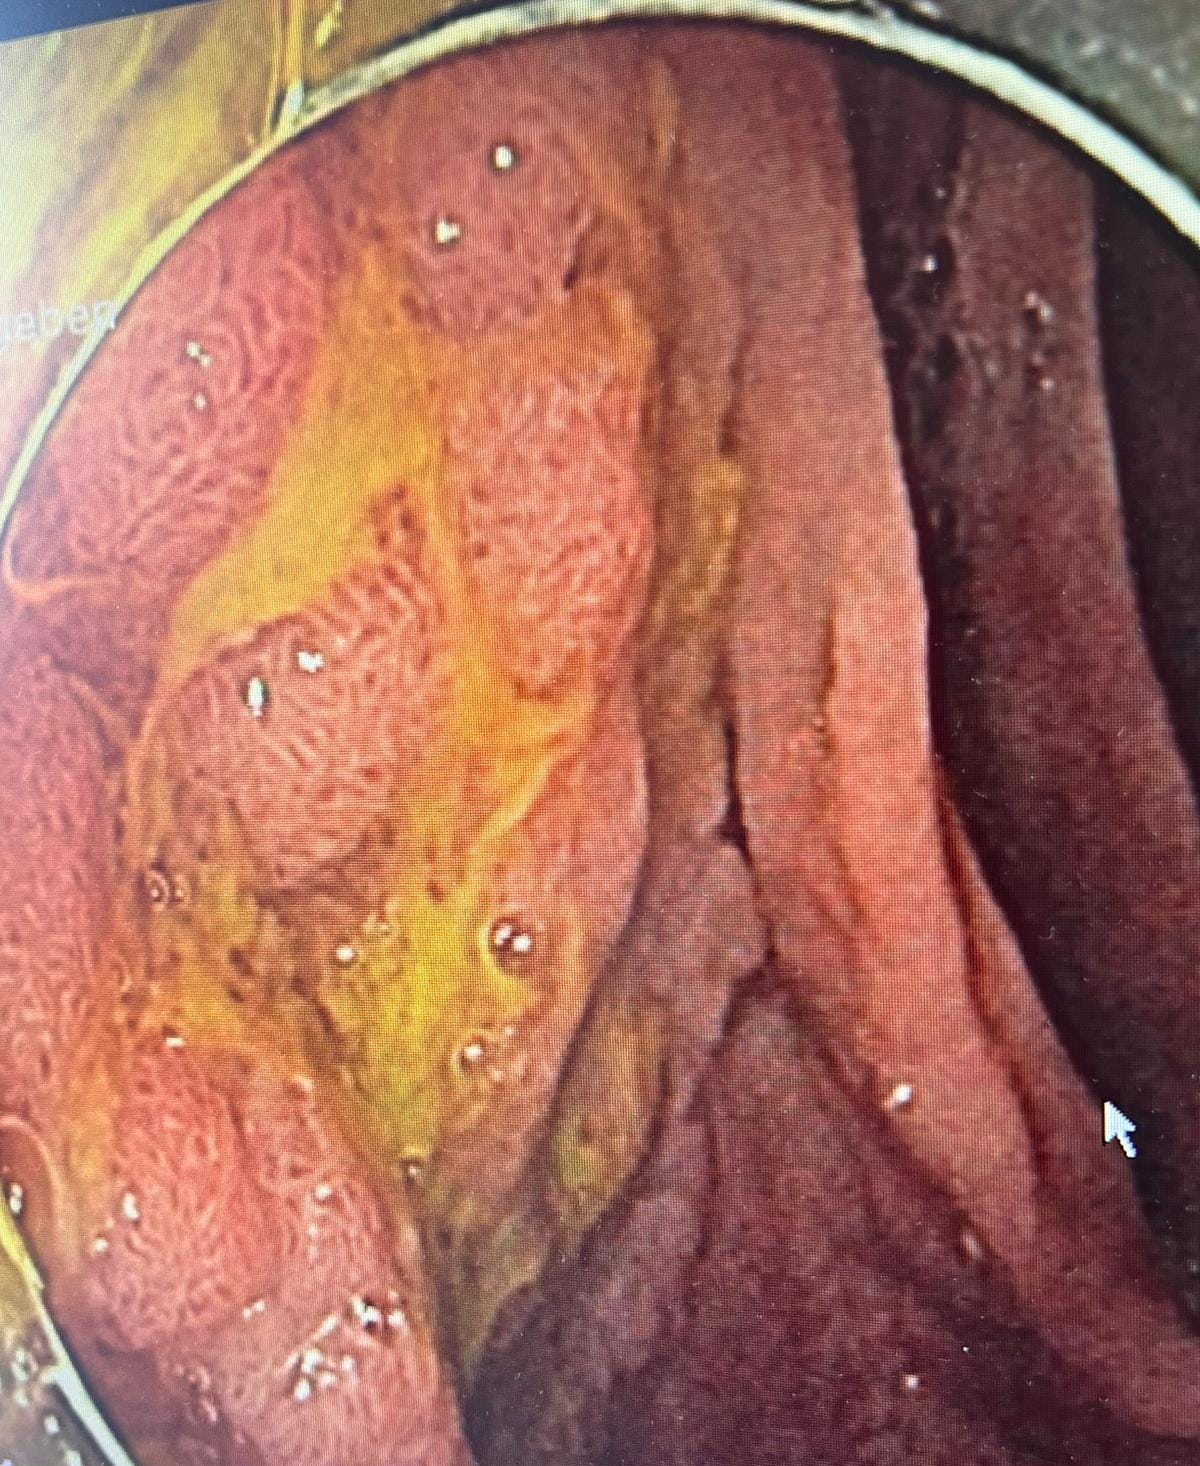

Case 6: Severe Esophagitis - A Broad Differential

Case Summary: An 82-year-old diabetic and hypertensive woman presented with odynophagia and was found to have severe esophagitis, leading to a wide-ranging differential diagnosis discussion.

Key Teaching Points:

• Comprehensive Differential: The group considered a broad differential, including:

• Boerhaave syndrome

• Severe GERD (Grade D)

• Drug-induced esophagitis (bisphosphonates, doxycycline, KCL)

• Infectious causes (CMV, HSV, Candida)

• Ischemia (Acute Esophageal Necrosis)

• Eosinophilic Esophagitis

• Vasculitis (Pemphigus, IgA)

• Acute Esophageal Necrosis: This rare entity, also known as “black esophagus,” was discussed as a possibility, especially in elderly patients with comorbidities. It typically affects the distal third of the esophagus.

• Diagnostic Workup: The recommended workup included a CT chest to rule out perforation, a thorough review of the patient’s drug history, and biopsies to rule out infectious or inflammatory causes.

• Initial Management: High-dose PPI (40mg BD) with a plan for a repeat EGD after healing was the recommended initial management.